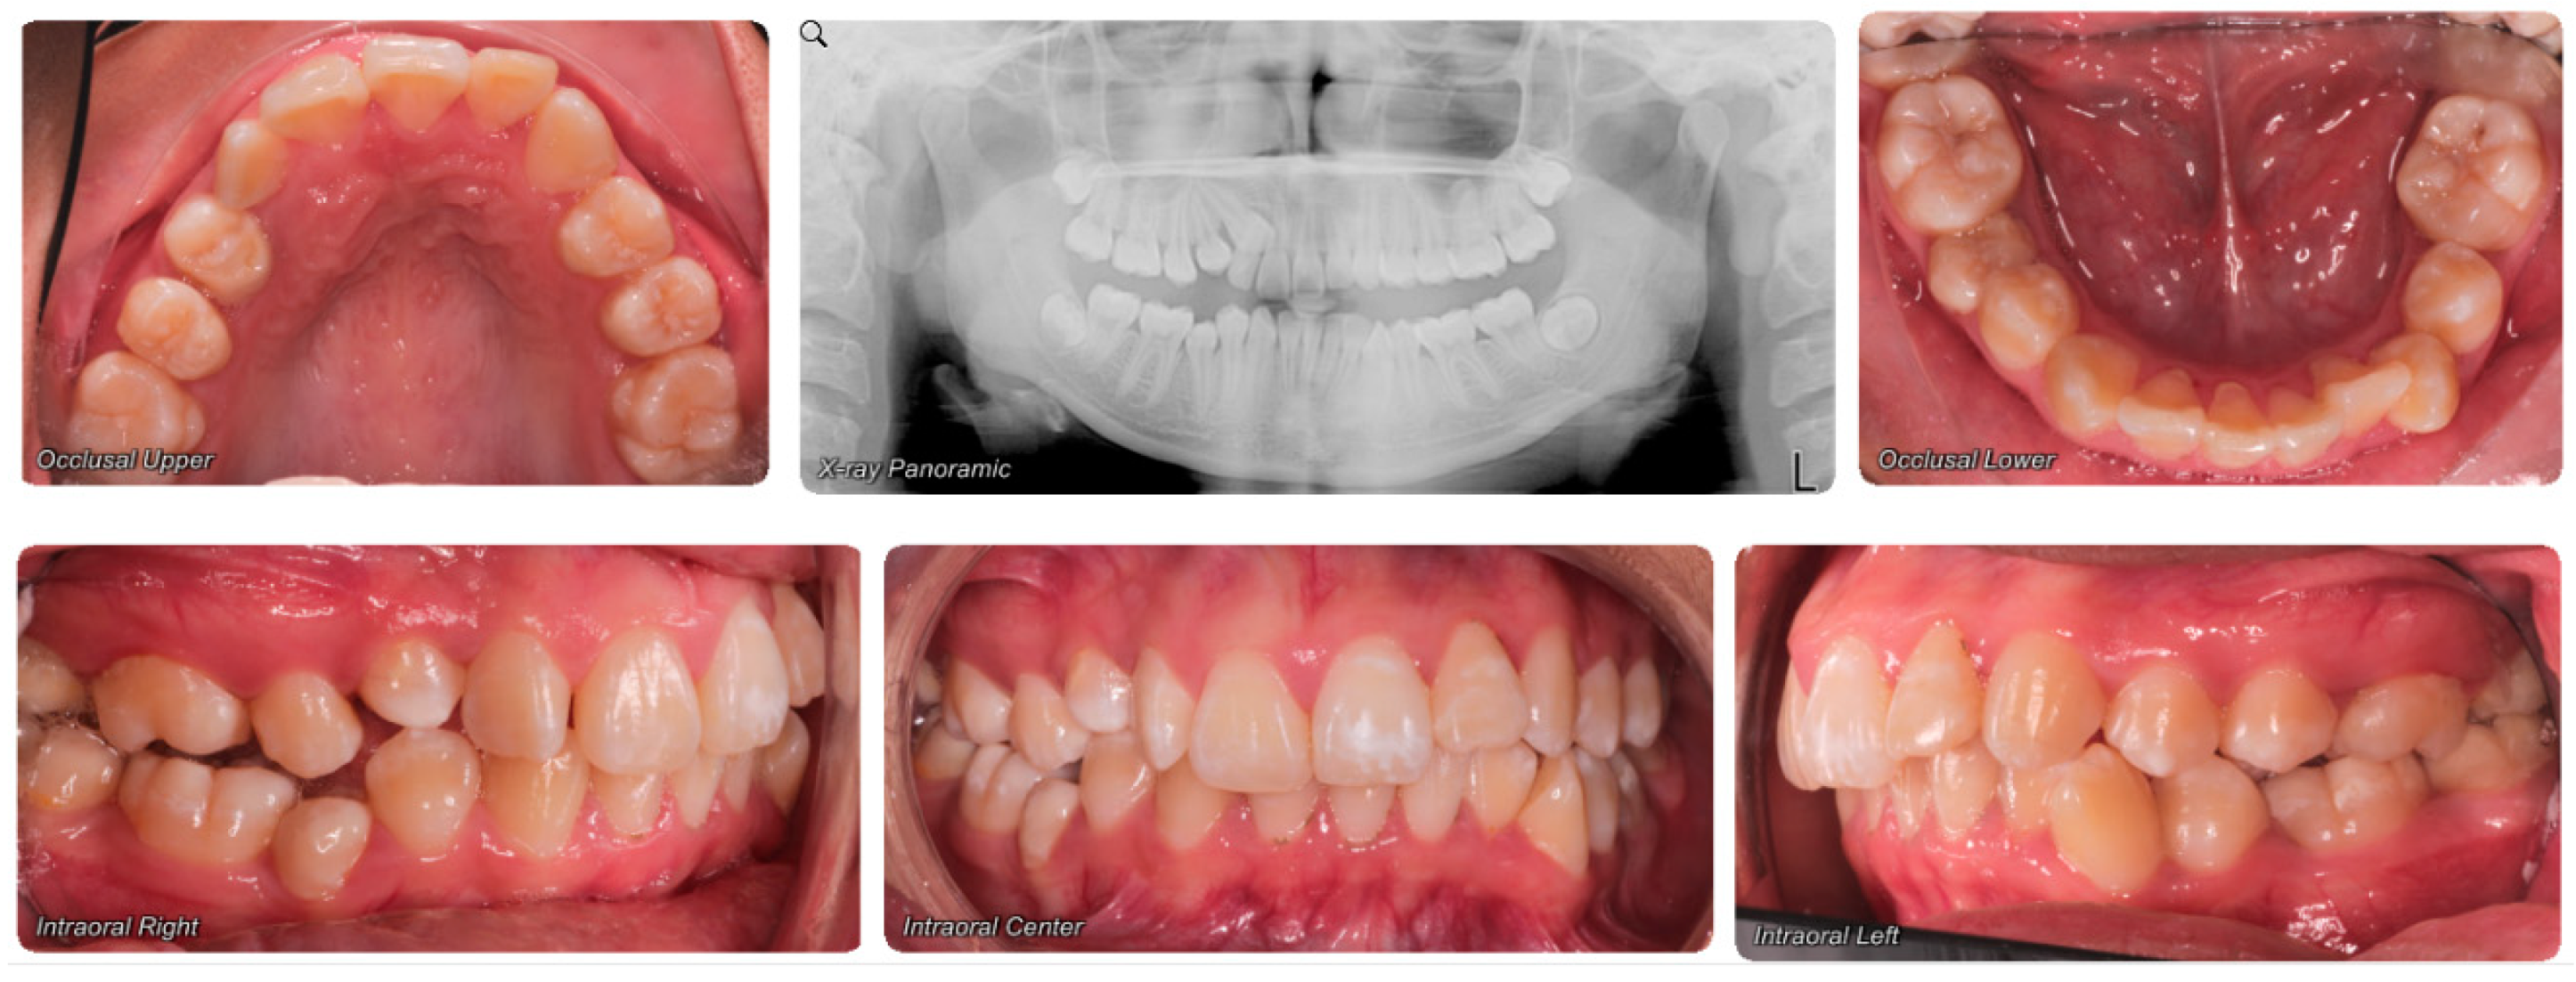

- Assessment of an impacted canine with close proximity to the lateral incisor. Figure 27 shows photographs and a panoramic radiograph of a case in which there is an impacted permanent maxillary right canine in an unfavorable position, a missing mandibular left second premolar and uncoordinated dental midlines. The relationship of the impacted canine to the adjacent lateral incisor cannot be determined from the conventional 2D radiograph. Therefore, CBCT was acquired. Figure 28 shows CBCT images, including coronal, sagittal, axial views, and volume rendering, which demonstrated close proximity of the impacted canine to the lateral incisor, and an area of bone loss buccal to the crown of the impacted canine. Before acquisition of CBCT, the tentative treatment plan was to extract the maxillary right first premolar and bring the canine to the dental arch. However, due to the findings presented by CBCT, the treatment plan was altered in favor of extracting the impacted canine, a clinical decision that was strongly favored by the patient. In this case, the first premolar would substitute for the canine. The maxillary left first premolar and mandibular right first premolar were also extracted. Therefore, each quadrant would have one missing tooth by end of treatment. Orthodontic post-treatment photographs are presented in Figure 29. Figure 30 shows a post-treatment 2D panoramic radiograph. CBCT was neither necessary nor indicated at completion of orthodontic treatment, and therefore only a conventional 2D panoramic radiograph was taken.